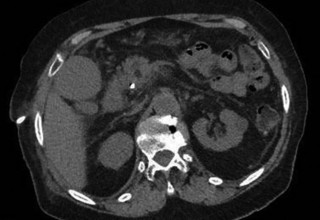

Figure 1.

Doctors at Zaragoza University Hospitals in Spain successfully utilized microwave energy to minimally invasively treat extrahepatic bile duct tumor obstruction.

The doctors at Zaragoza University Hospital in Spain applied microwave energy to destroy tumor growth within the main bile duct to reestablish and maintain normal bile flow. A flexible catheter with a microwave antenna tip is inserted into the liver under fluoroscopy into the bile duct with blockages. Once the antenna is positioned in the blockage, microwave energy is applied using preset power, temperature and time durations endocavitary. The antenna is pulled along within the duct with the blockage, and the energy application is repeated until the desired length of the duct is treated. The doctors removed the microwave catheter and verify bile-duct flow with fluoroscopy.  Doctors place resorbable prosthesis, dilation stent balloon, and 5F catheter for 24hrs. No complications were observed. The microwave energy application is controlled with direct temperature feedback from the ablation antenna during the procedure to ensure safety and efficacy.

AveCure® microwave ablation system is successfully treating tumors in bile-duct using a minimally invasive technique, the percutaneous transhepatic cholangiography (PTC) incision through the skin to access the tumor through liver, and patient is left with a small hole in the skin which quickly heals with almost no scar after the procedure.  AveCure® system utilizes a smart antenna in either probe or catheter format and microwave energy controller to select the correct size, temperature, and timer settings appropriate for safe, effective and predictable treatment.